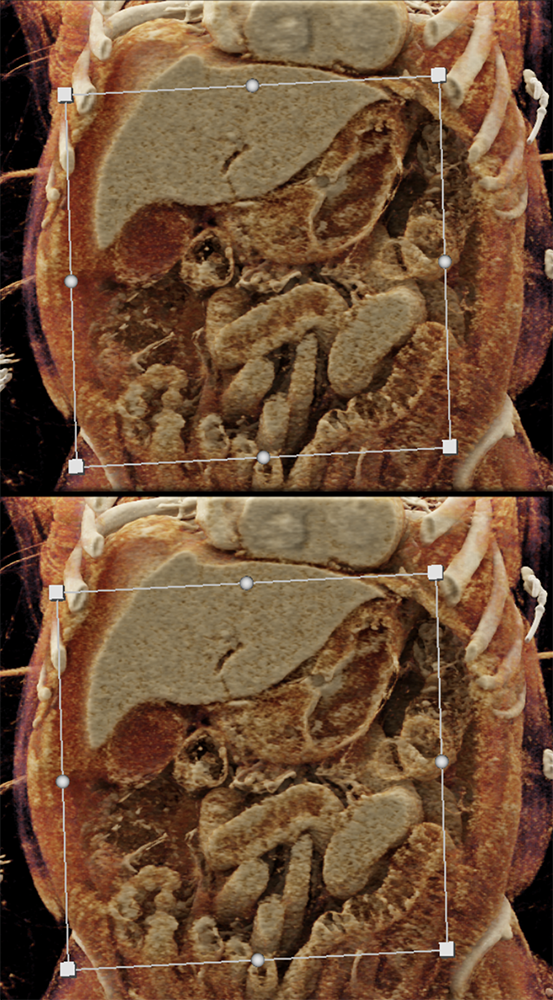

Watermelon stomach (WMS), or gastric antral vascular ectasia (GAVE) ![]() |

“In our patient, the findings of prominent mucosal folds extending from the pylonic channel on upper gastrointestinal series and the thickened antral wall on CT scans correlate well with the known pathologic appearance of gastnic antral vascular ectasia. Histologically, antral thickening results from a combination of foveolar and fibromuscular hyperplasia. Grossly, the antral fold prominence appears to result from bunching of the mucosa in the thickened, hypercontractile antrum.” Gastric antral vascular ectasia ("watermelon stomach"): radiologic findings. Urban BA, Jones B, Fishman EK, Kern SE, Ravich WJ. Radiology. 1991 Feb;178(2):517-8. |

“Gastric antral vascular ectasia primanily affects women (9:1 female-to-male ratio) aged 56-76 years, and is associated with liver cirrhosis (37%) and achlorhydnia (35%). The usual symptoms are iron-deficiency anemia and melena due to chronic gastrointestinal bleeding from the dilated, superficial, and easily traumatized vessels. Antrectomy is curative, but endoscopic treatment with heat probes or lasers has shown promise.” Gastric antral vascular ectasia ("watermelon stomach"): radiologic findings. Urban BA, Jones B, Fishman EK, Kern SE, Ravich WJ. Radiology. 1991 Feb;178(2):517-8. |